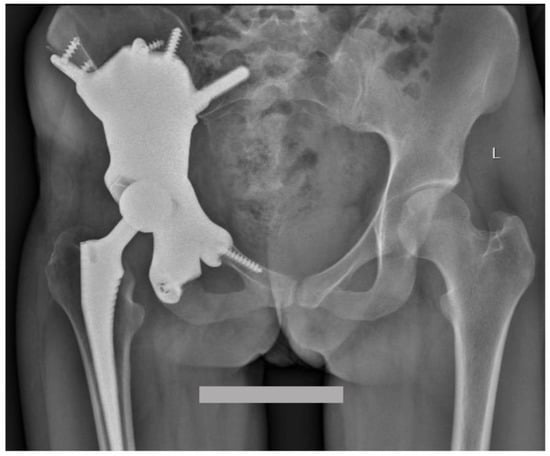

Custom-Made 3D-Printed Prosthesis after Resection of a Voluminous Giant Cell Tumour Recurrence in Pelvis

2. Case Presentation